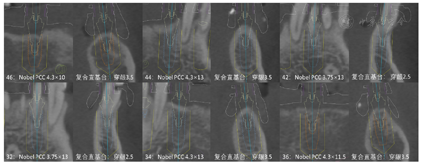

治疗过程:(1)术前准备:①藻酸盐取初印模,制作个性化托盘(图4);②用个性化托盘取硅橡胶终印模,灌制终模型;③制作光固化树脂

架;④排牙,制作放射导板(图6A);⑤试戴放射导板(图6B~D),拍摄两次CBCT(患者佩戴放射导板拍摄CBCT以及放射导板单独拍摄CBCT)。(2)方案设计:①将两次CBCT获取的DICOM数据导入种植设计软件重叠(图7),以修复为导向指导上下颌种植体位置摆放(图8、图9);②生成并打印手术导板(图10)。(3)利用手术导板和导板锁,翻制模型,制作临时修复体(图11)。(4)一期手术过程:铺巾消毒,局麻后拔除上下颌余留牙,搔刮拔牙窝内炎性肉芽组织,于34-36、44-46区牙槽嵴顶近远中向切开牙龈,翻瓣。就位并固定手术导板,于11、13、16、22、25、26、32、34、36、42、44、46定点,按术前设计方案植入NobelParallelTM ConicalConnection种植体。除26区种植体外,其余种植体初期稳定性均达到35N.cm以上,就位复合基台,戴入保护帽,修整牙龈黏膜,缝合牙龈(图12A~F)。术后拍摄全景片(图13)。次日复诊,取下保护帽,戴入预制的临时修复体,调合(图12G)。

治疗结果:术后3个月全景片显示种植体骨结合良好(图14)。26牙行二期手术,就位复合基台,戴入保护帽。两周后,取下临时修复体,制取上下颌硅橡胶印模,利用临时修复体交叉上

架转移患者颌位关系。设计数字化桥架(图15),切削铝制支架。试戴铝制支架,拍摄全景片显示支架被动就位良好(图16)。按照铝制支架切削纯钛支架,上聚合瓷,患者右侧咬合空间不足,设计金属